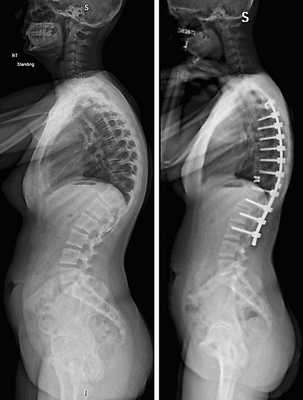

Коррекция кифоза грудного отдела.

Лечение сколиоза 3 степени

Сколиоз 3 степени характеризуется дугой деформации позвоночной оси с углом от 26 до 40 градусов. В отличие от сколиоза 1 и 2 степени деформация позвоночника 3 степени это серьезное нарушение биомеханики позвоночника. Кроме того, риск прогрессирование при сколиозе 3 степени составляет 68%. Поэтому, своевременное полноценное лечение сколиоза 3 степени позволит приостановить дальнейшее прогрессирование деформации и в определенной степени стабилизировать функциональность позвоночника .

Примечательно, что диагноз «сколиоз 3-й степени» может быть установлен только после оценки рентгеновских снимков позвоночника в соответствии с методом Кобба. Метод включает проведение двух линий, которые параллельны позвоночным концевым пластинам тел позвонков. В точке их пересечения измеряется угол.

В зависимости от возраста пациента и тяжести искривления, рекомендуются различные виды хирургического вмешательства. Цели каждой из этих операций - остановить прогрессирование и попытаться уменьшить угол искривления ,наряду с улучшением осанки пациента.

Наиболее распространенными из них являются операции с использованием стержней и слияния. При этом методе два или более позвонков сращиваются , чтобы создать единый жесткий сегмент позвоночника, который больше не способен двигаться. Стержни из различных стальных сплавов прикрепляются непосредственно к костям позвоночника для стабилизации области спондилодеза.